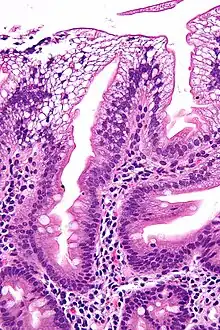

There is an absence of apolipoprotein B. On intestinal biopsy, vacuoles containing lipids are seen in enterocytes. This disorder may also result in fat accumulation in the liver (hepatic steatosis). Because the epithelial cells of the bowel lack the ability to place fats into chylomicrons, lipids accumulate at the surface of the cell, crowding the functions that are necessary for proper absorption.

Micrograph showing enterocytes with a clear cytoplasm (due to lipid accumulation) characteristic of abetalipoproteinemia. Duodenal biopsy. H&E stain. -

Duodenal biopsy from ABL individual shows vacuolated enterocytes